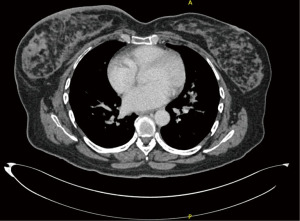

Retrospectively, we reviewed the patient’s mammogram, MRI and CT scan. All the images were consistent with a bilateral RS which is more obvious on the right side as the muscle fibers were longer and wider (Figures 2-4).